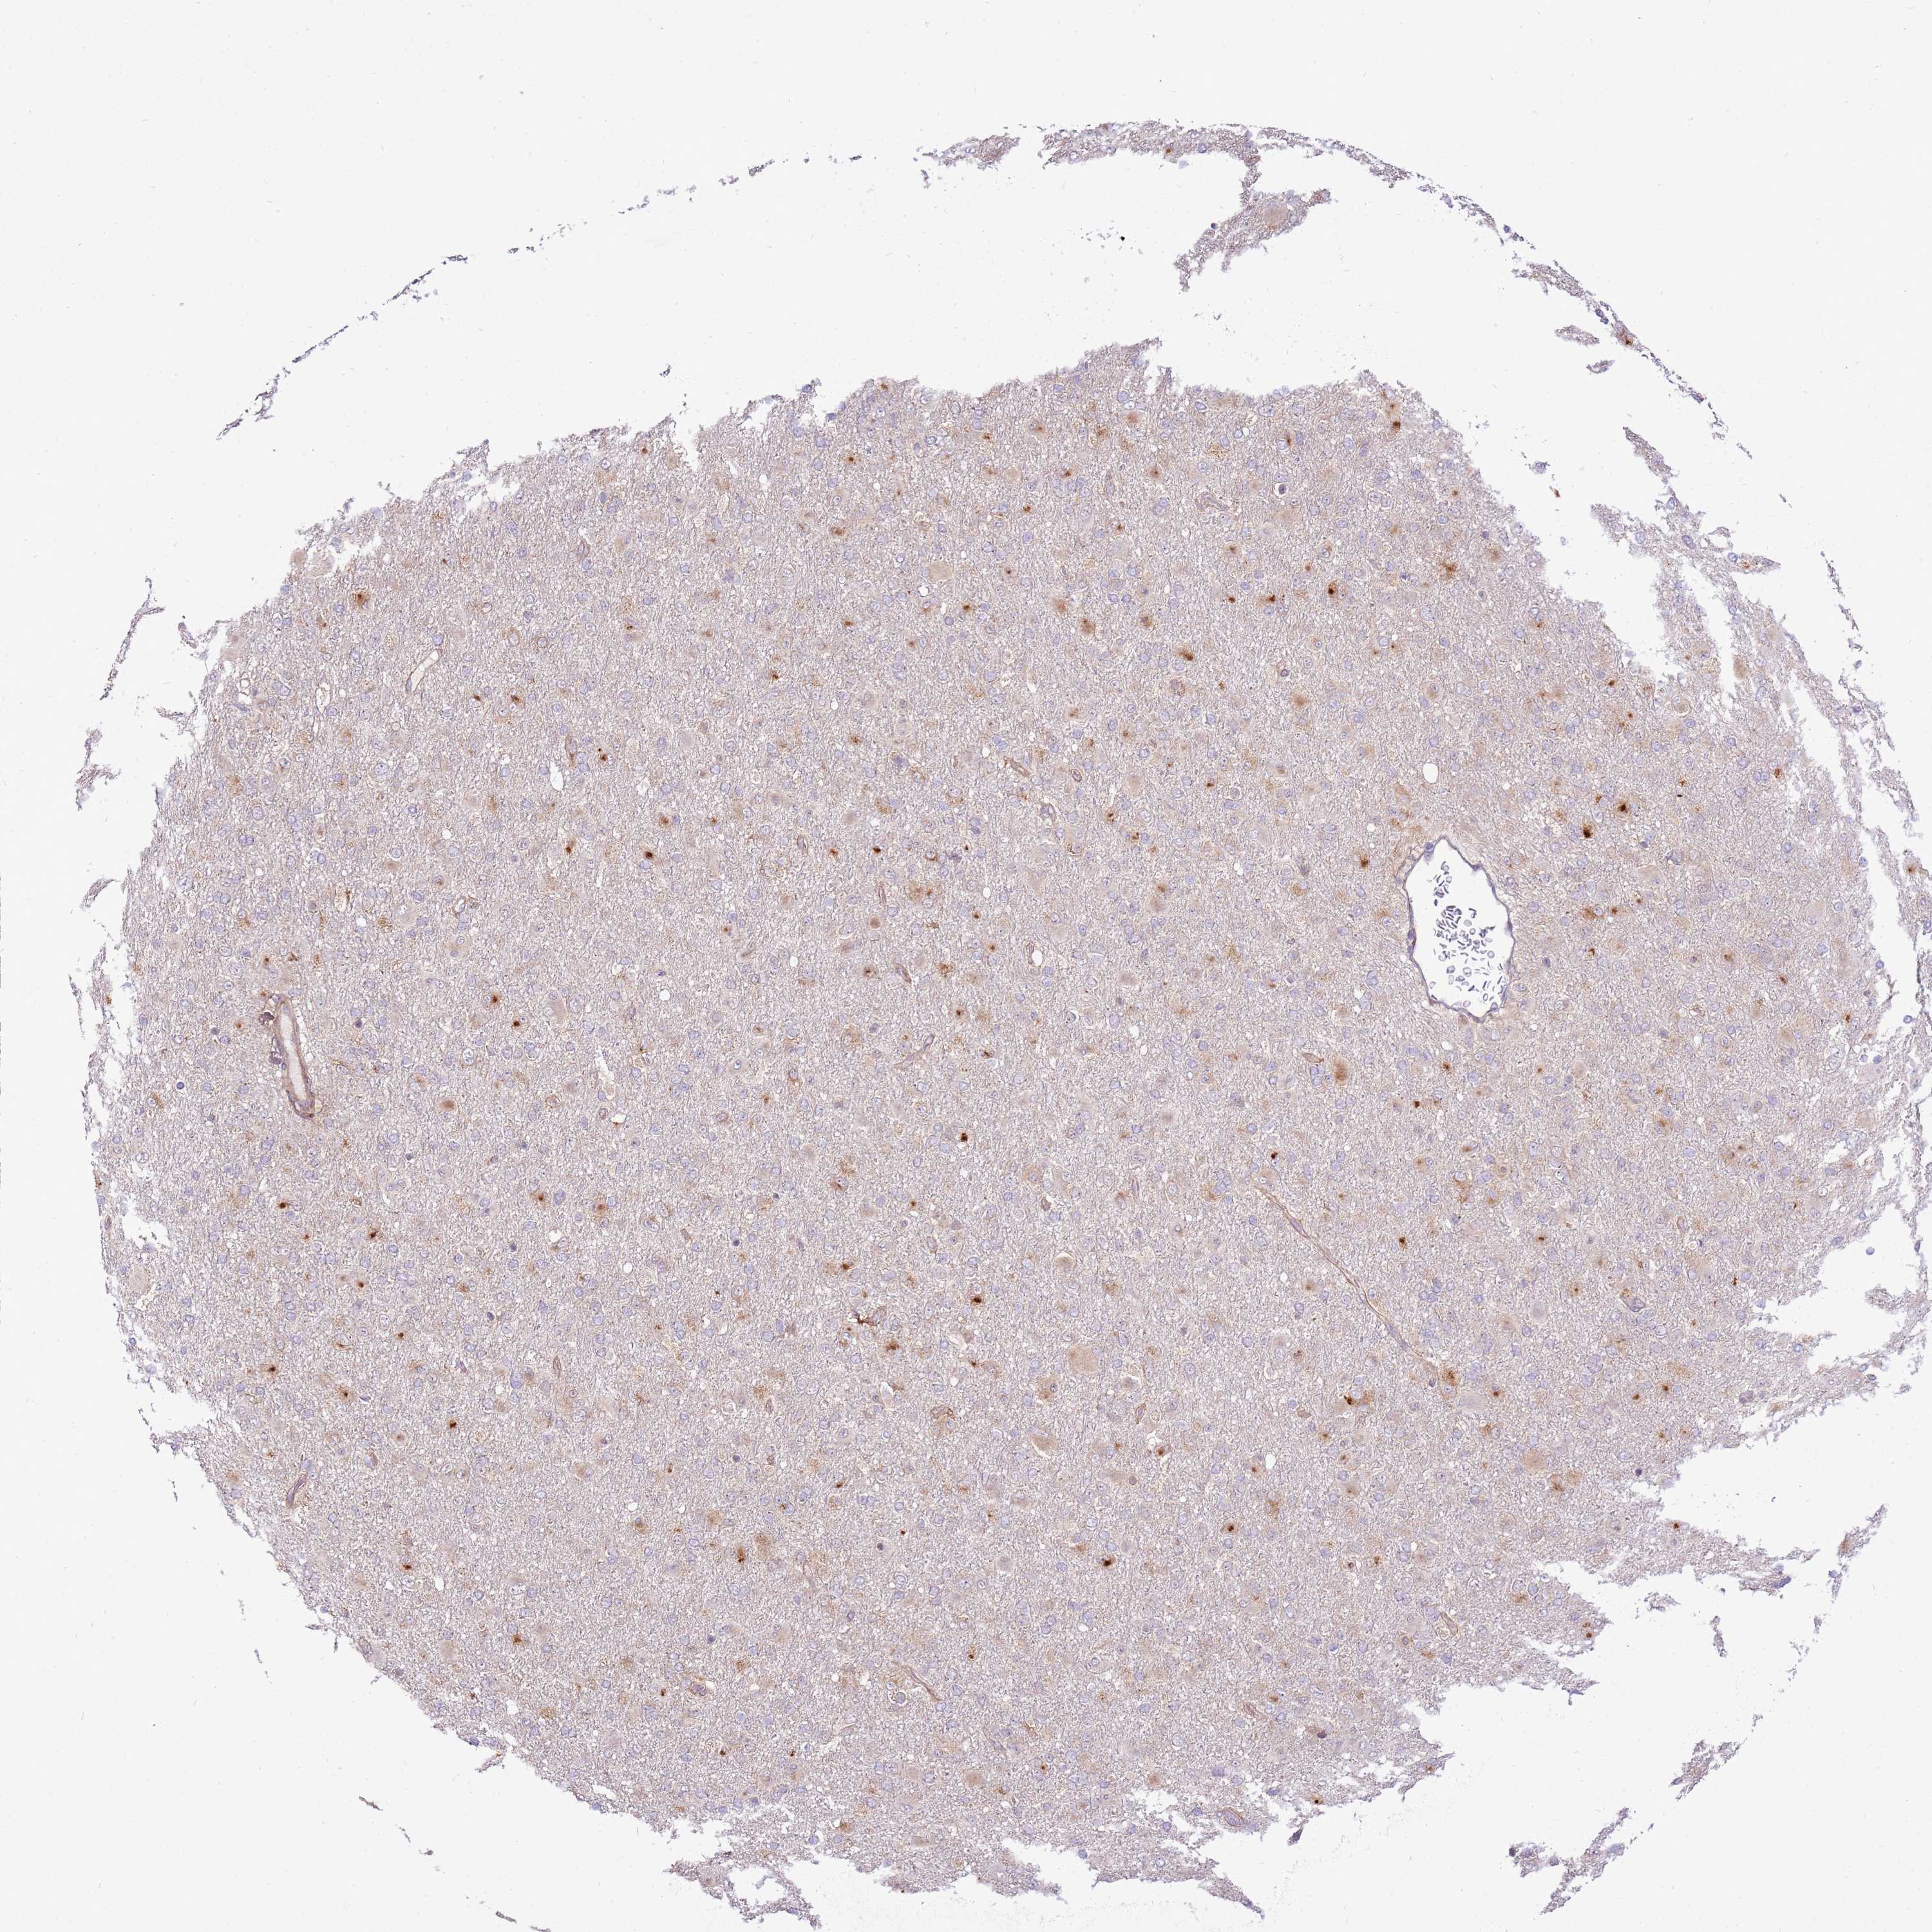

GLIOMA - Protein expressioni

A mouse-over function shows sample information and annotation data. Click on an image to view it in a full screen mode. Samples can be filtered based on level of antibody staining by selecting one or several of the following categories: high, medium, low and not detected. The assay and annotation is described here.

Note that samples used for immunohistochemistry by the Human Protein Atlas do not correspond to samples in the TCGA dataset.

Antibody stainingi

Antibody staining in the annotated cell types in the current human tissue is reported as not detected, low, medium, or high, based on conventional immunohistochemistry profiling in selected tissues. This score is based on the combination of the staining intensity and fraction of stained cells.

Each image is clickable and will lead to virtual microscopy that enables deeper exploration of all samples and also displays staining intensity scores, fraction scores and subcellular localization as well as patient and tissue information for each sample.

Antibody HPA047386

Staining

High

Medium

Low

Not detected

Intensity

Strong

Moderate

Weak

Negative

Quantity

>75%

75%-25%

<25%

None

Location

Nuclear

Cytoplasmic/membranous

Cytoplasmic/membranous,nuclear

Glioma, malignant, High grade

Glioma, malignant, Low grade